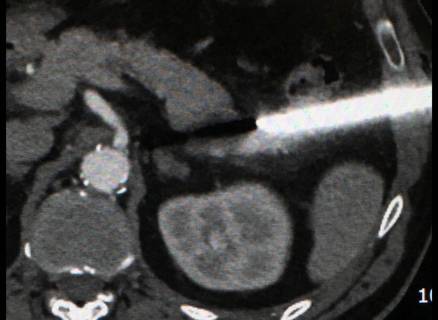

L’agobiopsia è una procedura mediante la quale viene prelevato del materiale biologico (cellule o liquidi nel caso dell’agoaspirato, frammenti di tessuto nel caso dell’agobiopsia) per eseguire esami cito-istologici, microbiologici e molecolari. La procedura viene eseguita in anestesia locale, sotto guida ecografica o tac, in regime ambulatoriale per organi superficiali (tiroide, linfonodi superficiali, mammella), di day hospital in caso di strutture profonde (polmone, fegato, rene, pancreas etc). La diagnosi consentirà di attuare una strategia terapeutica specifica per ciascun tipo di patologia.

In anestesia locale, sotto guida per lo più ecografica o tac, viene inserito un sottile ago all’interno della lesione ed estratto un frustolo di materiale che viene immerso in una soluzione di formalina ed inviato in laboratorio.

Generalmente si ottengono più campioni in punti diversi della lesione attraverso una unica puntura, tramite l’utilizzo di una cannula che viene lasciata in situ sino al termine della procedura; estratta, infine, la cannula ed eseguita la medicazione viene praticato il controllo radiologico finale al termine del quale il paziente potrà tornare in reparto.